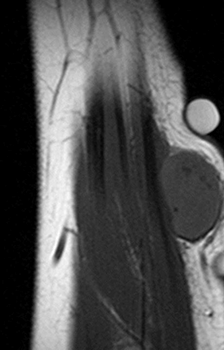

МРТ, как неинвазивный метод исследования, полезен для определения локализации для биопсии, мониторинга течения и оценки результатов лечения.23

- МРТ стопы (назначается при подозрении на разрыв подошвенной фасции).